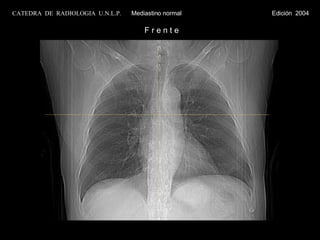

CATEDRA  DE  RADIOLOGIA  U.N.L.P.   Mediastino normal  Edición  2004 F r e n t e